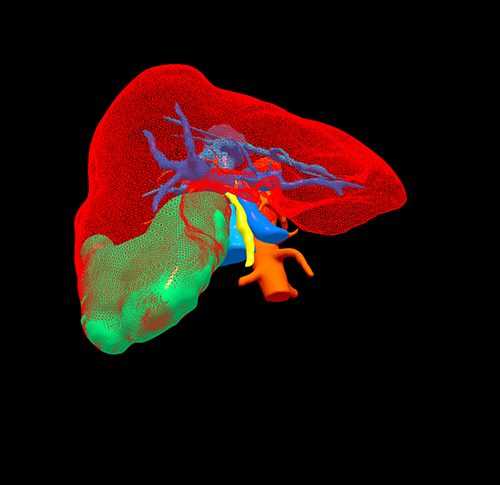

手术规划--右半肝切除,门静脉取癌栓